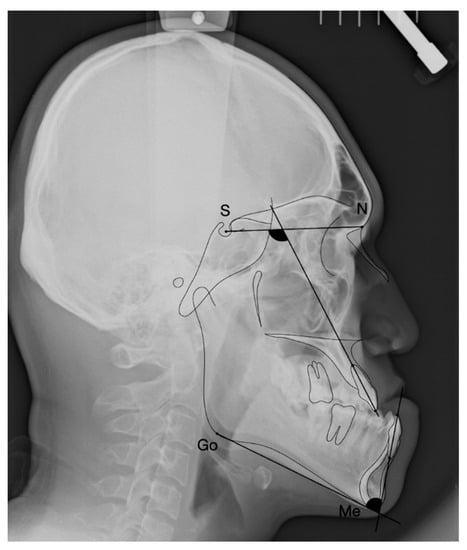

2.3. Variables of Cephalometric Measurements